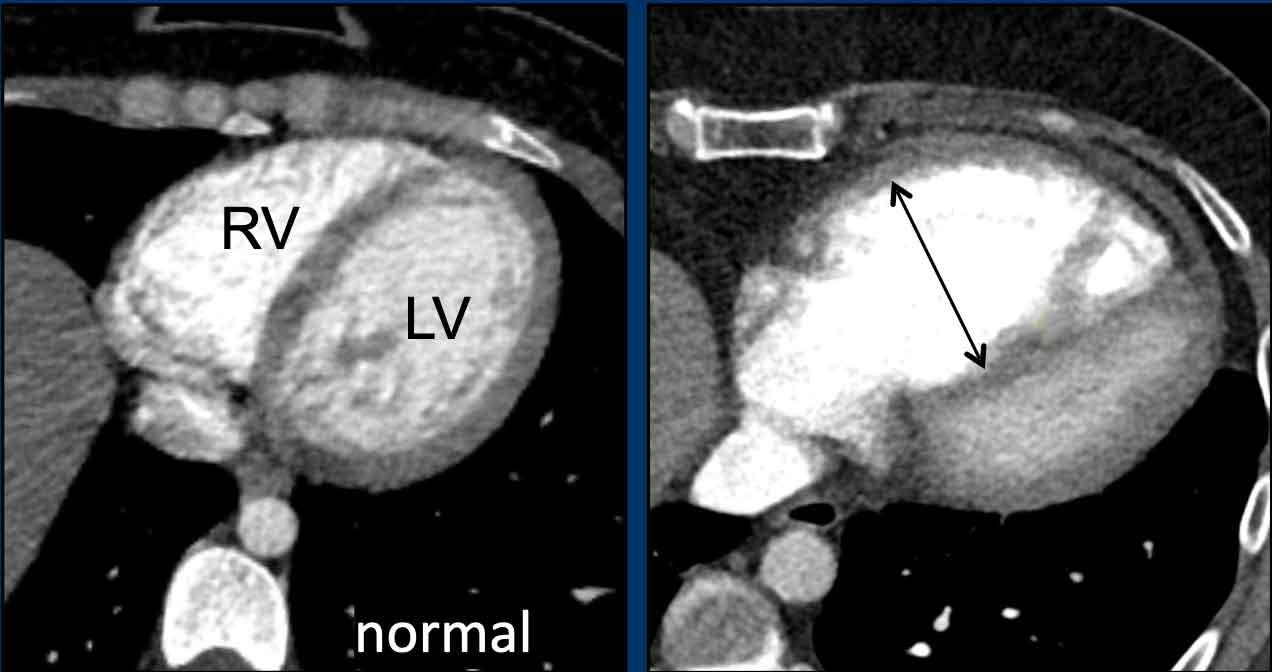

Giãn Thất Phải

Các hình ảnh cho thấy thất phải và thất trái bình thường so với thất phải bị giãn.

Các giá trị ngưỡng được đề xuất để đánh giá giãn tim phải trên CT lát cắt ngang:

- Nhĩ phải: ≥ 65mm (nữ) và ≥ 70mm (nam)

- Thất phải: ≥ 55mm (nữ) và ≥ 60mm (nam)

Trên mặt cắt trục ngắn, thất trái bình thường có hình dạng tròn đến bầu dục.

Vách liên thất góp phần tạo nên đường viền tròn của thành tâm thất.

Vách liên thất bị dẹt hoặc vồng sang trái là dấu hiệu chỉ điểm quá tải áp lực và giãn thất phải.